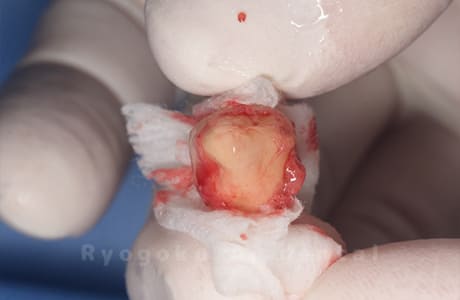

Case27

移植する親知らず

-

- 原因

- 重度カリエス

- 治療内容

- 自家歯牙移植、部分矯正

- 治療費用

- 220,000円(移植費用)

110,000円(部分矯正費用)

虫歯が大きく、保存不可能となった歯を上の親知らずと交換する自家歯牙移植を行いました。移植歯が小ぶりであったため、部分矯正を行い問題なく噛み合い、経過良好です。